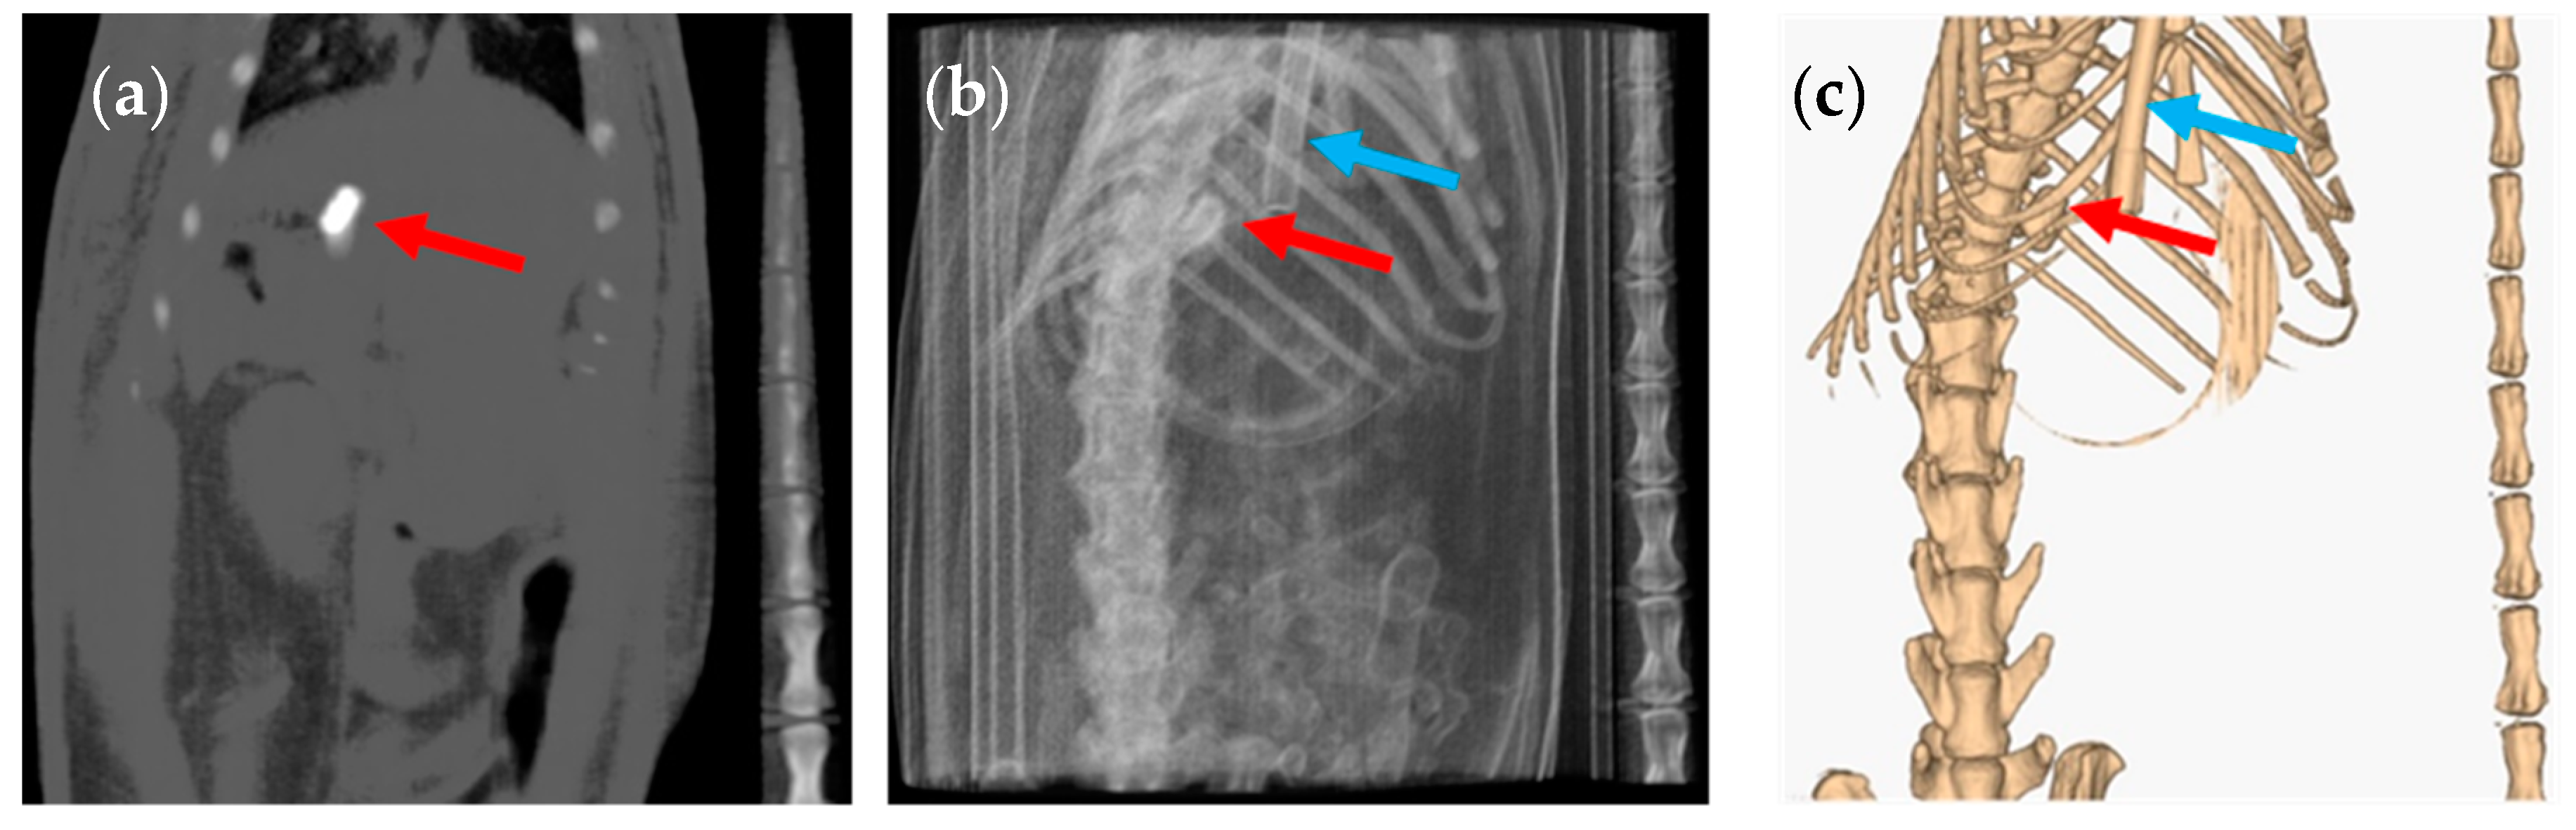

3. Results and Discussion